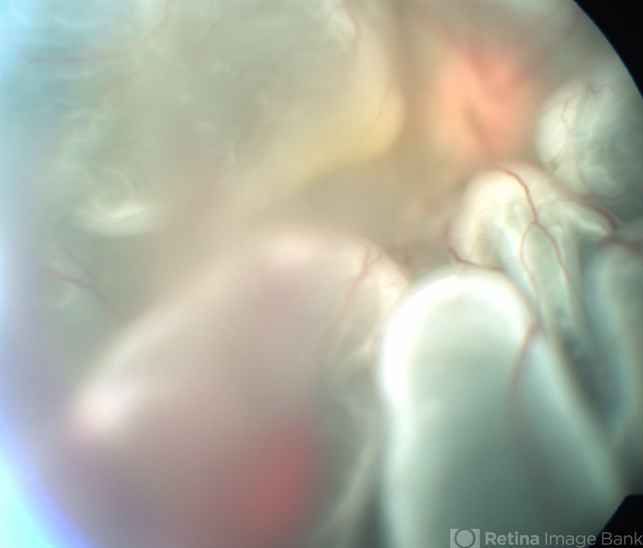

- A 60-year-old male presented to us with complaint of Diminished vision and on examination he was found to have retinal detachment with choroidal effusion.